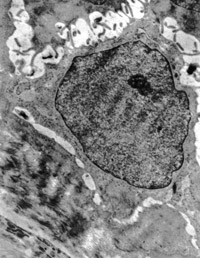

5-2-8 傷后第10天,皮膚附件上皮細(xì)胞成簇分布,核仁邊集,內(nèi)質(zhì)網(wǎng)擴(kuò)張,胞質(zhì)內(nèi)含較多張力原纖維  TEM×6000